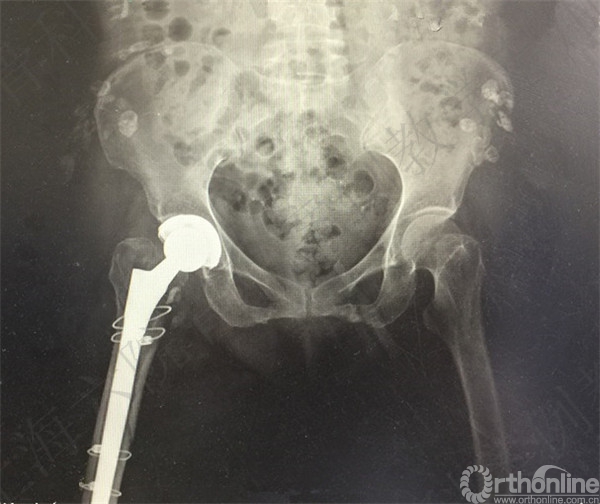

此类患者依从性较差,第一次术后医方应充分告知,嘱咐并强调相关注意事项,必要时转下级医院继续康复治疗。假体脱位手法复位后,未能明确排除是否存在假体松动。医方存在对术后并发症观察、处理不当,告知缺陷等过失。